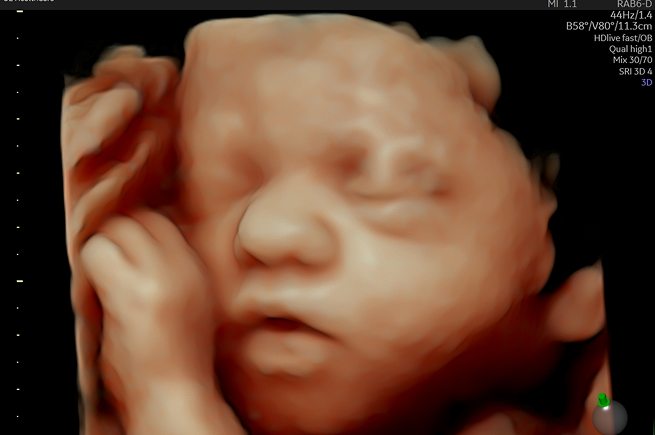

입체 초음파 (3D)

양수량이 풍부하고 태아의 피하지방이 발달하는 시기에, 아기의 얼굴과 표정, 움직임을 실제 사진이나 영상처럼 입체적으로 확인합니다. 출산 전 아기와의 애착을 깊게 형성할 수 있는 감동적인 검사입니다.